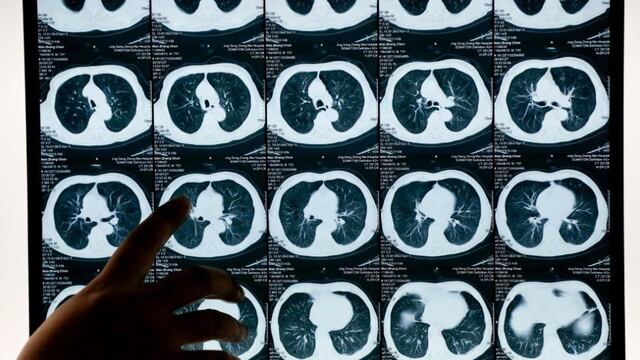

Un equipo de investigadores españoles descubrió un nuevo tratamiento, denominado Nadim, que ha arrojado resultados “sorprendentes”, pues ha curado del cáncer de pulmón al 80 por ciento de los pacientes que lo probaron.

El nuevo avance, desarrollado por investigadores del Grupo Español de Cáncer de Pulmón (GECP), fue presentado en el Congreso Mundial de Cáncer de Pulmón, que se celebra desde el pasado 7 de septiembre y concluye este martes en Fira de Barcelona.